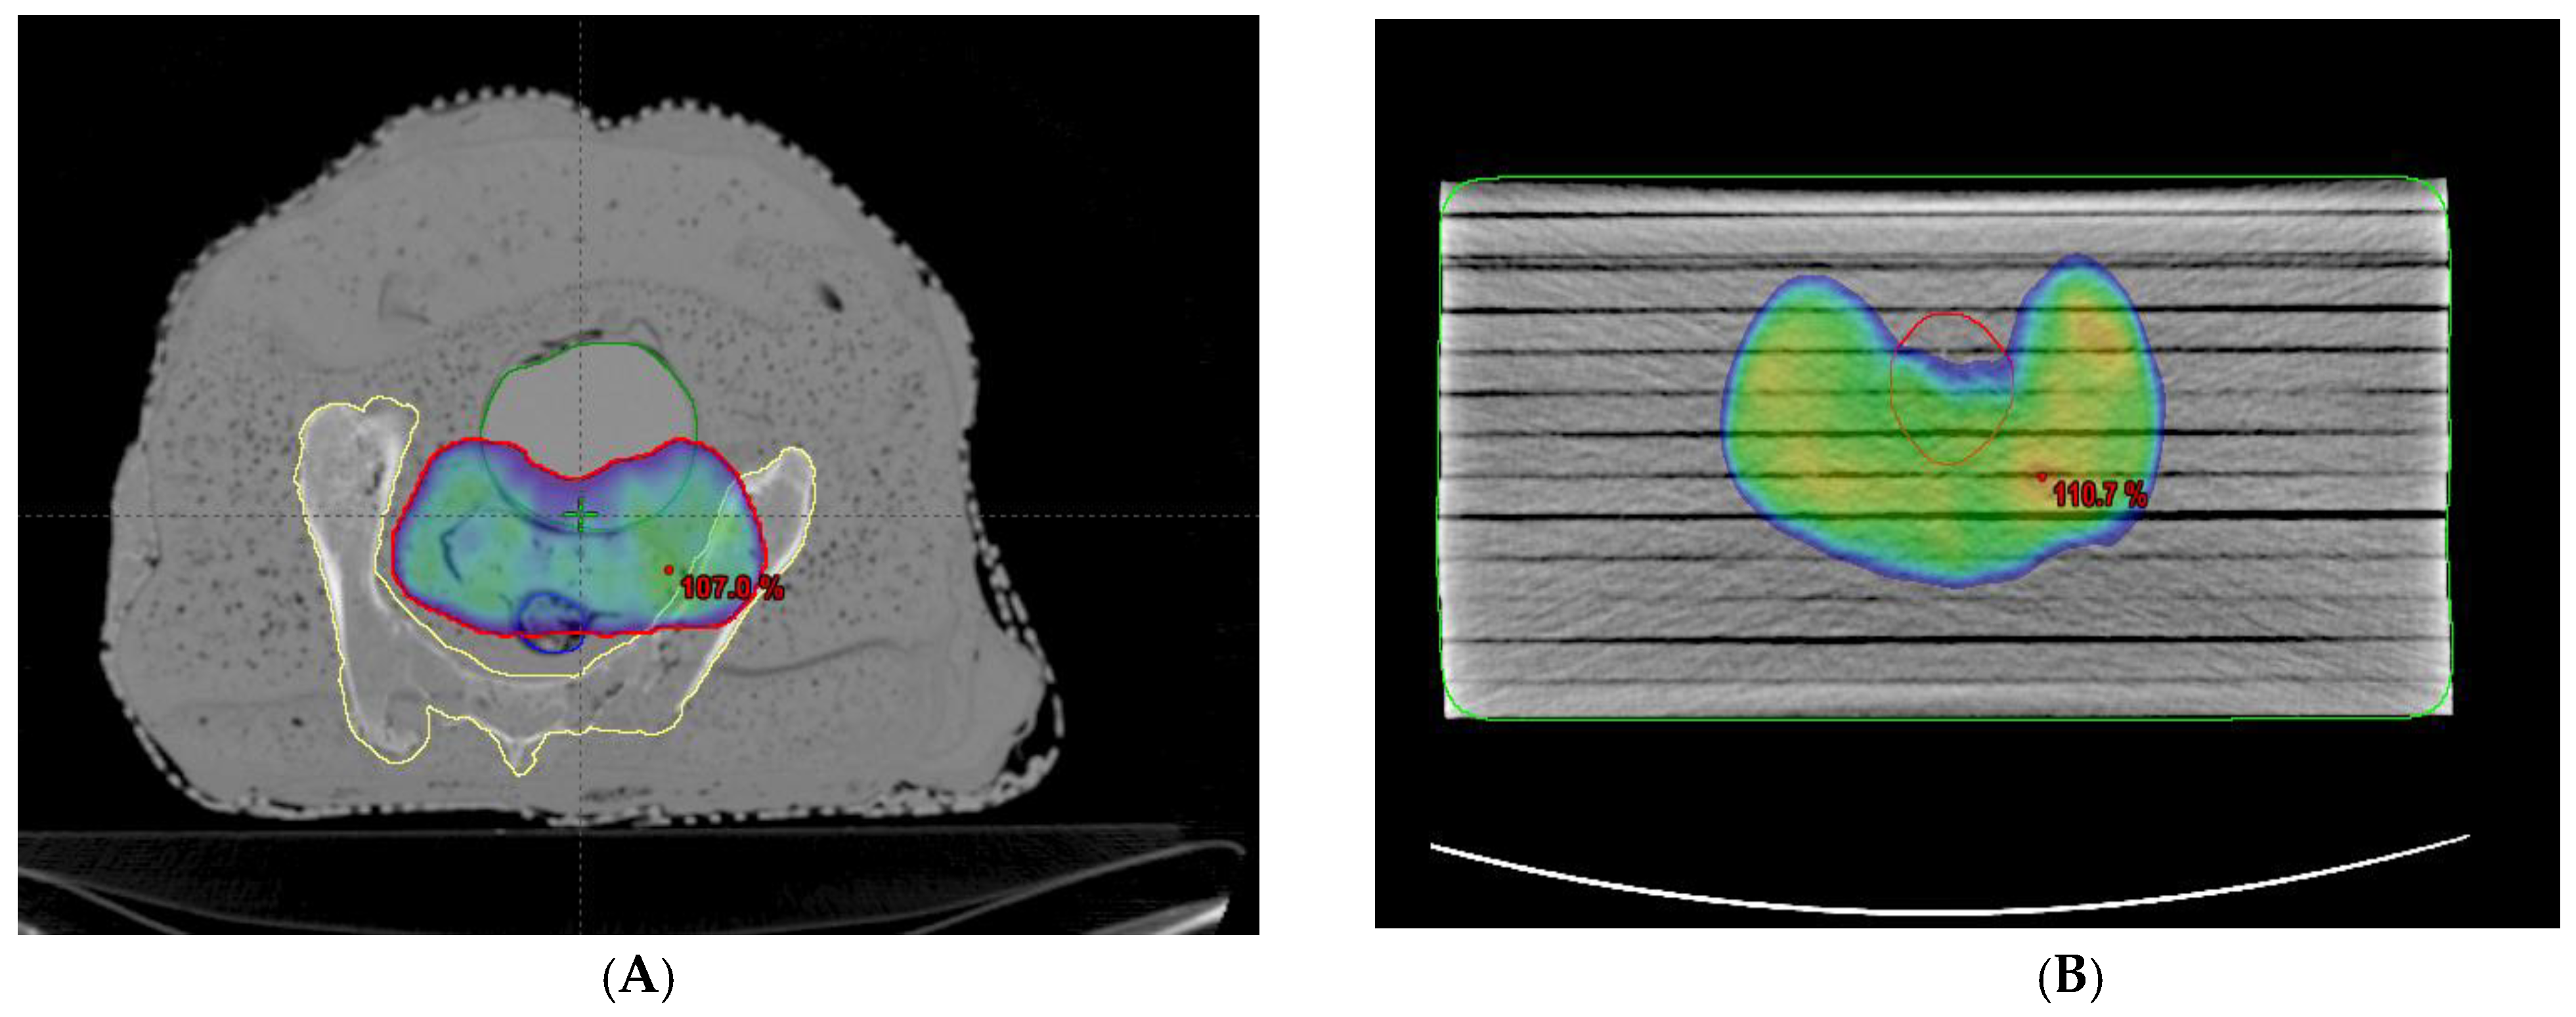

Two kinds of phantoms were chosen for the patient-specific absolute dosimetry of the completed RapidArc treatment plans. The first one was a homogeneous “water-equivalent RW3 solid phantom” (PTW Freiburg, Freiburg, Germany), as shown in Figure 1B, each slab of which was made of polystyrene with the effective atomic number 5.74. The second phantom was the AHFP phantom, as shown in Figure 1A. The density of the internal organs of this AHFP phantom was equivalent to that of the human pelvis. The CT scanning of the phantoms was conducted on a Toshiba Alexion 16 multi-slice CT scanner, with a slice thickness of 2 mm for planning purposes. The CT images were imported into the Eclipse (version 11.0.31) TPS (Varian Medical Systems, Palo Alto, CA, USA), and RapidArc plans already conducted for patient treatment were exported into both phantoms, which can be seen in Figure 3A,B.

Figure 3.

(A,B) RapidArc plan representation on the AHFP phantom and homogeneous (RW3) phantom with dose coverage of 95% of prescribed.

Thirty cervical cancer patients who underwent RapidArc therapy, ranging in age from 37 to 70 years (average 53.5 years), were selected randomly for the study. Dual arcs were used for all the RapidArc plans since dual arcs can improve PTV coverage, enhance the modulation factor during optimization, and spare the OARs compared to single arcs. The first arc was a clockwise rotation with a gantry angle of 181° to 179° and a collimation angle of 30°. The second arc had a collimation angle of 330° and an anticlockwise rotation with gantry angles of 179° to 181°. All the selected plans were performed with a 6 MV photon beam, and field arrangement was conducted in such a way that all fields were coplanar with a couch angle of 0°. A dose volume optimizer (DVO) was used for plan optimization, and an anisotropic analytical algorithm (AAA) (version 11.30.1) with a grid size of 0.25 cm was used for dose calculation. All the plans were delivered, and the dose for each plan was measured using a PTW UNIDOSE electrometer connected with a 0.6 cc ionization chamber (IBA Dosimetry Germany), which was fixed in phantoms.